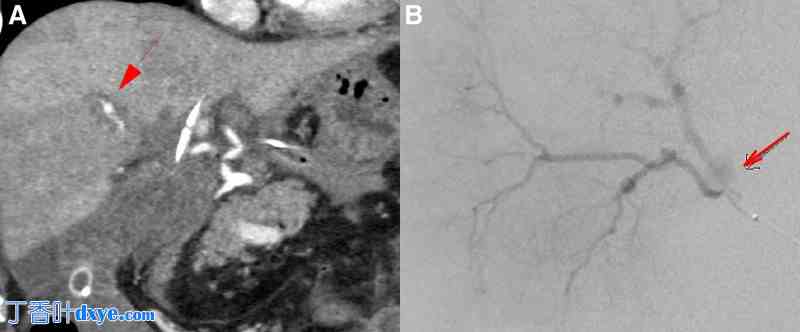

一名 44 岁男性患者因反复出现胆管炎和黄疸,从之前的医院转诊至进一步评估。患者报告 2 年前在院接受胆管肠吻合术,因为他在另一家医院接受腹腔镜胆囊切除术时胆管损伤导致胆汁漏出,随后接受胆管肠吻合术治疗。患者在胆道重建术后第 6 天出现胆管出血和突然出现剧烈腹痛。急诊 CT 显示肝动脉动脉瘤破裂(A8;图 1A)。因此,患者接受了 IVR 治疗(图 1B)。此后,患者恢复顺利,并在之前的医院定期随访。

图 1.

胆道重建术后观察到胆道出血。 (A) 提示增强 CT 扫描,结果显示肝内动脉瘤 (➡)。(B) 实施了紧急 IVR。血管造影显示 A8 肝动脉动脉瘤破裂 (➡),该动脉瘤 2 年前已成功栓塞止血。CT = 计算机断层扫描,IVR = 介入放射学。